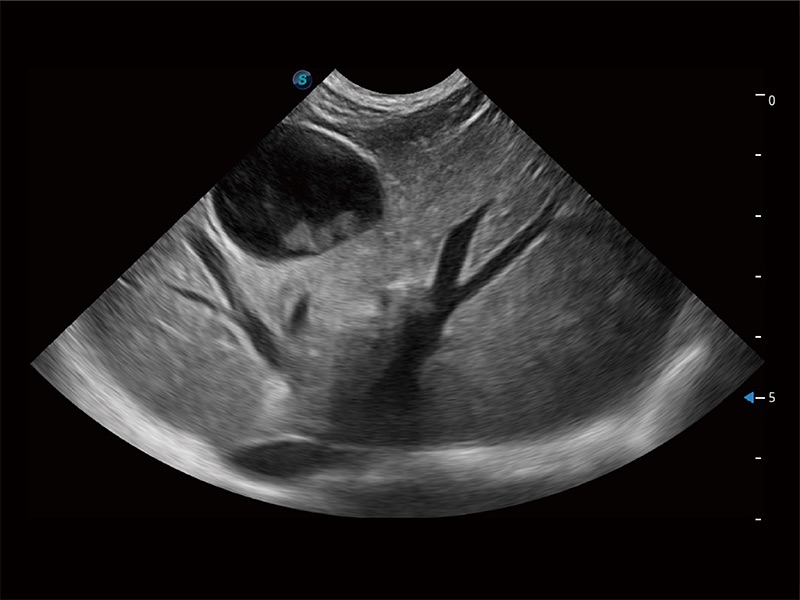

(犬)肝脏

(猫)胆囊